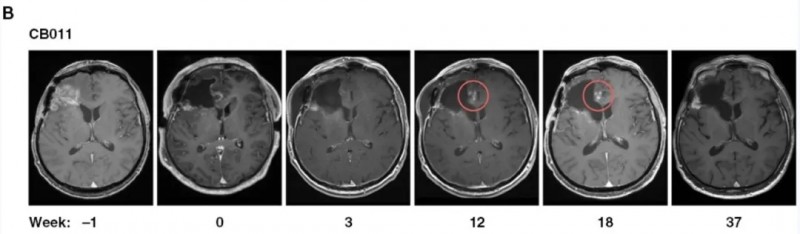

术后联用CAR-NK细胞疗法!助复发性胶质母细胞瘤患者创近3年生存奇迹

全球知名期刊《神经肿瘤学(Neuro-Oncology)》近期发表了一项Ⅰ期临床试验数据,聚焦CAR-NK细胞治疗复发性HER2阳性胶质母细胞瘤(GB)。9例可评估疗效的患者,在复发手术期间接受了手术腔边缘注射CAR-NK细胞治疗。

结果显示:9例入组患者的中位总生存期(OS)达31周,中位无进展生存期(PFS)为7周;其中2例出现假性进展的患者,OS分别长达98周和135周,PFS均为37周(详见下图)。

此外,56%的患者在复发手术联合7~37周CAR-NK治疗后达到病情稳定(SD)。值得注意的是,2例患者在注射部位出现假性进展,提示存在治疗诱导的免疫反应。MRI检查显示,CAR-NK注射后第12周,患者切除边缘附近出现斑点状对比增强,且该现象在后续几周内自行消失,推测与诱导的免疫反应相关,无需额外治疗(详见下图)。

▲图源“Neuro-Oncology”,版权归原作者所有,如无意中侵犯了知识产权,请联系我们删除